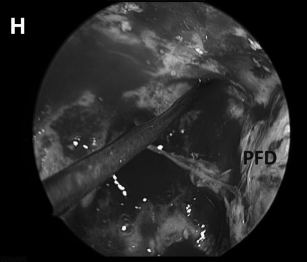

▼(H)术野侧面、后面方向为面神经所在。

▼(L)使用鼻中隔瓣(NSF)完成封闭。CC,囊包膜;PFD,后颅窝硬脑膜;S,蝶鞍;T,肿瘤。